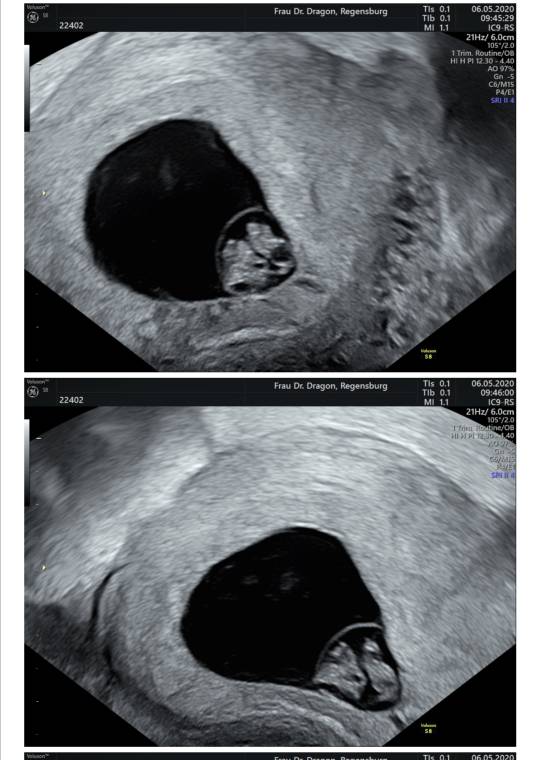

Cześć Dziewczyny. Czytam Wasze posty już od jakiegoś czasu. Nie pisałam wcześniej, ponieważ jeszcze boję się podzielić szczęściem jakie nas spotkało. Może trochę opowiem Wam moja historię. O maleństwo staramy się prawie 6 lat. Raz udało nam się zajść w ciążę ale niestety pęcherzyk ciążowy był pusty. Bardzo to przeżyliśmy. Gdy zrobiłam test nie wierzyłam, że są dwie kreski. Jestem w 7+4. Boję się bardzo, że może coś pójść nie tak. W 6+6 miałam USG lekarz na początku nie mógł znaleźć pęcherzyka strasznie się zdenerwowałam bo już raz mieliśmy taki scenariusz. Na szczęście okazało się, że jest i widać serduszko byłam szczęśliwa jak nigdy dotąd. Termin mam 26.12. Jeszcze boję się, że coś może pójść nie tak. Jednego dnia bardzo się cieszę, drugiego boję się bo może jeszcze coś pójść nie tak. Z dolegliwości mam wsumie tylko mdlosci, duży apetyt i dziwny posmak w ustach. Kolejną wizytę mam 22.05 i znów się strasznie boję. Pozdrawiam Was serdecznie.

Jest serducho [emoji3590] waliło jak oszalałe - mały człowiek we mnie mieszka [emoji7]

Słabo go trochę widać na zdjęciu przez moją tkankę tłuszczową hehe... trudno, najwyżej nie bedzie miec ladnych zdjęć w brzuchu póki co [emoji13]

Termin z USG na 31.12 - 01.01. [emoji3059] Będzie impreza [emoji4]

Za nic nie pamiętam ile ma długości...8,4 mm? Już nie słuchałam taka byłam zakręcona.